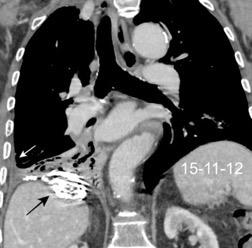

Nódulos pulmonares múltiples. (flechas verdes). Masas paratraqueales. (flechas amarillas). Dudoso ensanchamiento retrocrural (flechas negras). sigue….

Ttawfik A et al. Trans-diaphragmatic Pathologies: Anatomical Background and Spread of Disease on cross-sectional Imaging. Current Problems in Diagnostic Radiology. 2021.

T. mixto de células germinales del testículo

izquierdo Metástasis pulmonares. (flechas verdes). Ganglios paratraqueales. (flechas amarillas). Ganglios retroperitoneales (flechas negras)

Tawfik A et al. Trans-diaphragmatic Pathologies: Anatomical Background and Spread of Disease on cross-sectional Imaging. Current Problems in Diagnostic Radiology. 2021.